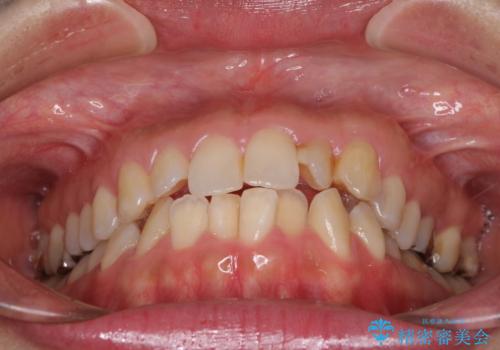

- 前歯の捻れを気にして来院された患者様です。

上顎前歯が捻れて前方に飛び出しており、下顎前歯もそれに沿うようにデコボコとなっていました。

IPR(歯と歯の間を削る処置)によりスペースを獲得して上下前歯のデコボコを改善し、インビザラインにて矯正治療を行うこととしました。